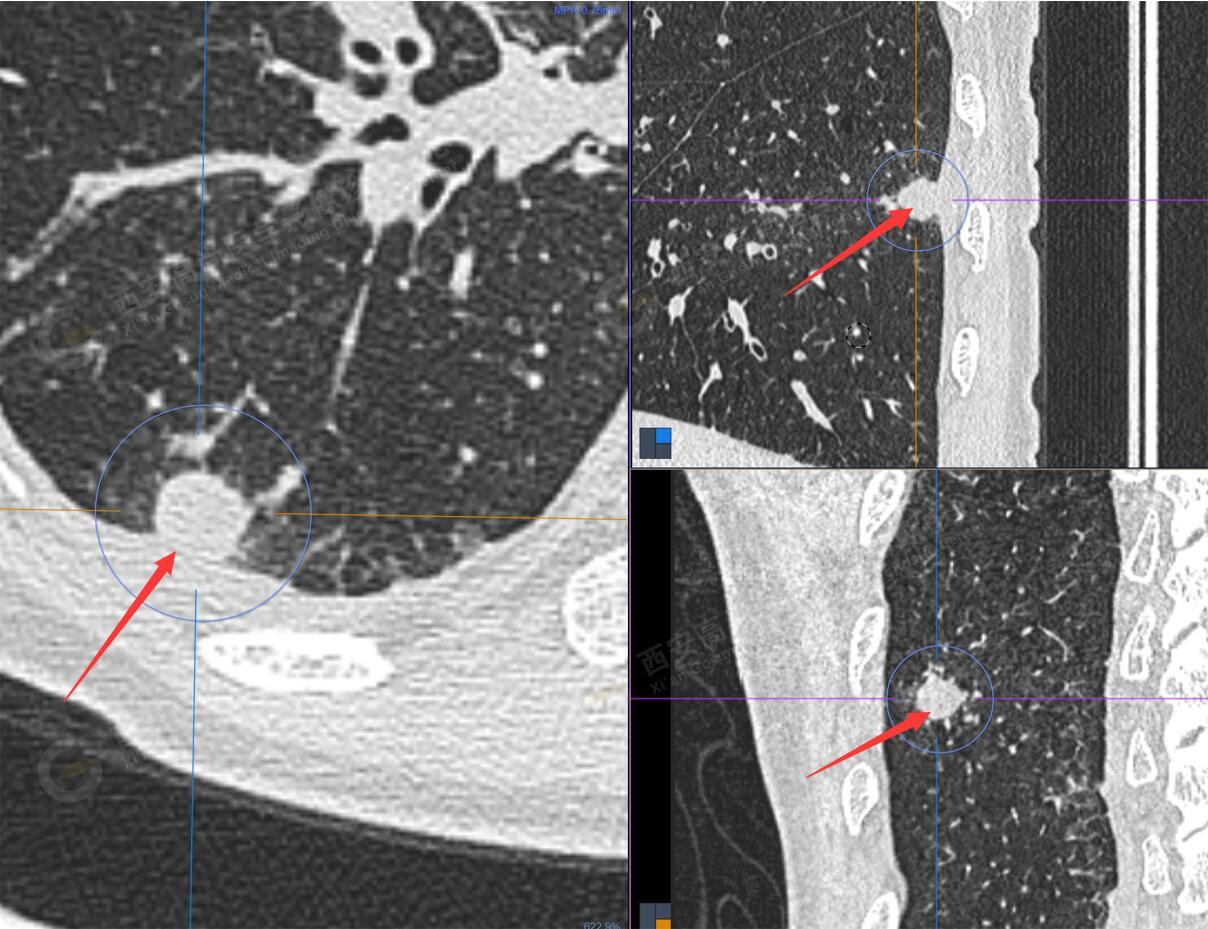

1.以下為肺內原發(fā)灶

1.右肺下葉后基底段軟組織結節(jié)(約1.5cm×1.2cm),與相鄰后胸膜分界不清,呈FDG代謝異常增高,結合病理,符合肺腺癌伴鄰近胸膜侵犯。